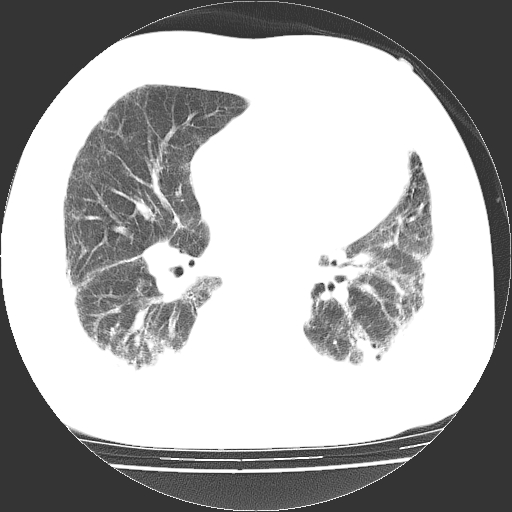

男,68岁,咳嗽、胸闷、发烧三天,查体:双肺散在湿罗音。

首先考虑特发型肺间质纤维化;两侧少量胸腔积液。

依据:1、两肺广泛条索状、网格状、蜂窝状改变。

双肺多发条索状、网格状及小灶状密度增高影。考虑慢支合并感染.间质纤维化,双侧少量胸腔积液

两肺广泛条索状、网格状、蜂窝状改变。肺间质纤维化,肺心病,双侧胸腔积液